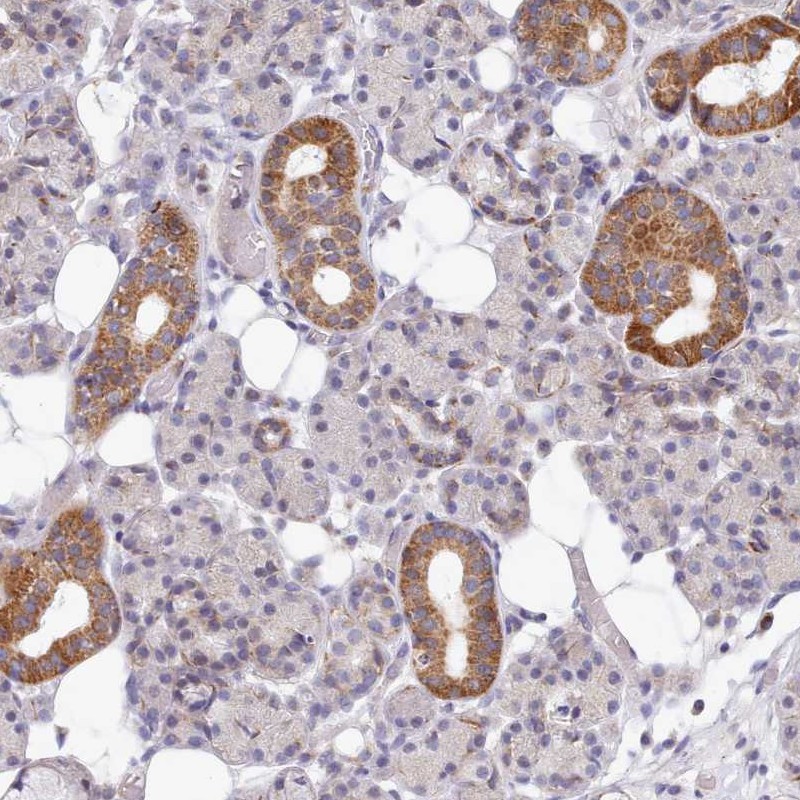

Immunohistochemical staining of human salivary gland shows granular cytoplasmic positivity in glandular cells.